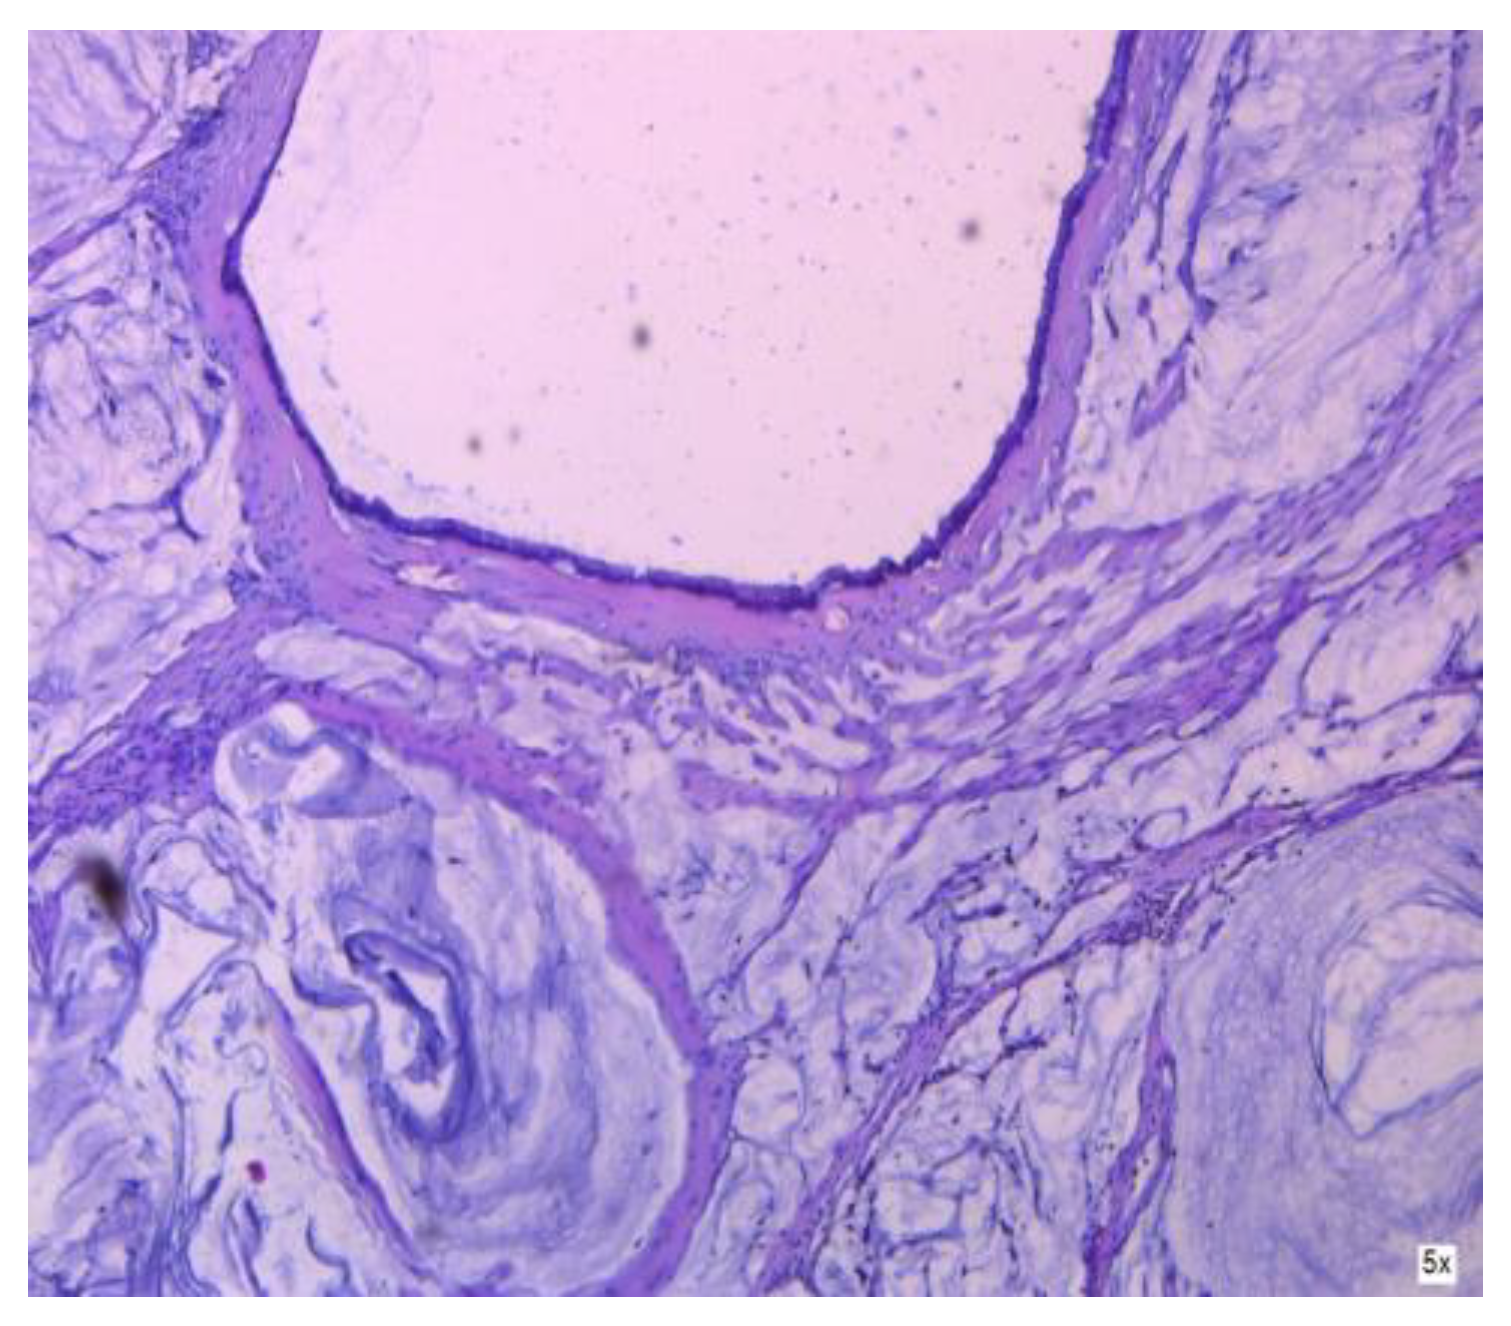

3.1.1. Mucinous Cystadenoma

3.2.2. Clinical and Pathology Findings